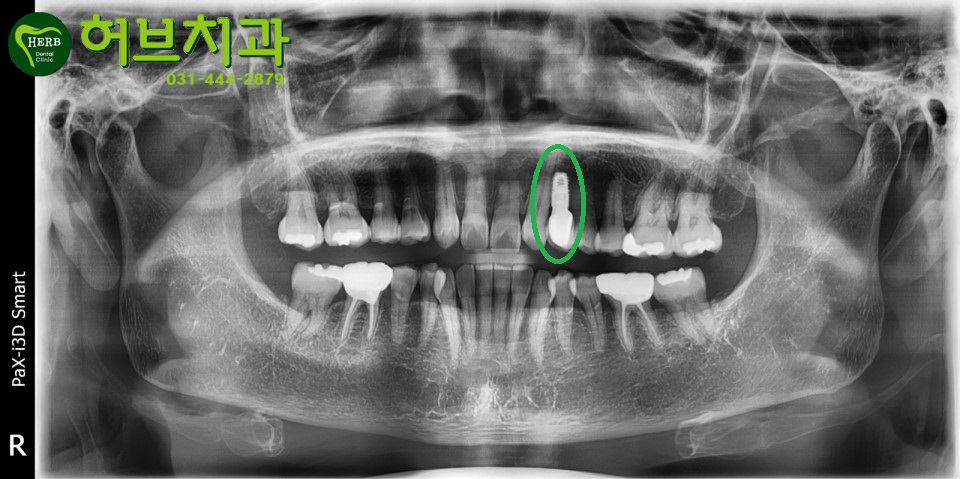

아래 사진의 환자분은 앞니가 태어날때부터 없으셨던 분입니다.

비어있는 앞니부분에 임플란트를 심으시기 위해 안양허브치과에 내원하셨습니다.

임플란트 심은 옆의 치아가 송곳니입니다.

송곳니를 끝부분과 옆면을 살짝 삭제해서 앞니모양으로 만들고

송곳니가 있어야 할 자리에 임플란트를 심어서

송곳니모양으로 치아를 만들어드렸습니다.

<선천적으로 앞니가 없으신 환자에게 임플란트를 심어드린 케이스1>